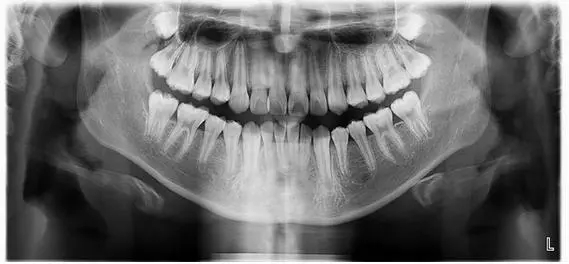

全景片

拍全景片是為(wei) 了解全口牙齒的數量以及畸形狀況。包括是否有多生牙、埋伏牙,牙根的位置、形態等好不好,還有重要的一點是牙槽骨的情況如何,牙周是否有炎症,是否滿足牙齒矯正的需求。拍全景片的價(jia) 格通常一兩(liang) 百元左右,不必擔心價(jia) 格。